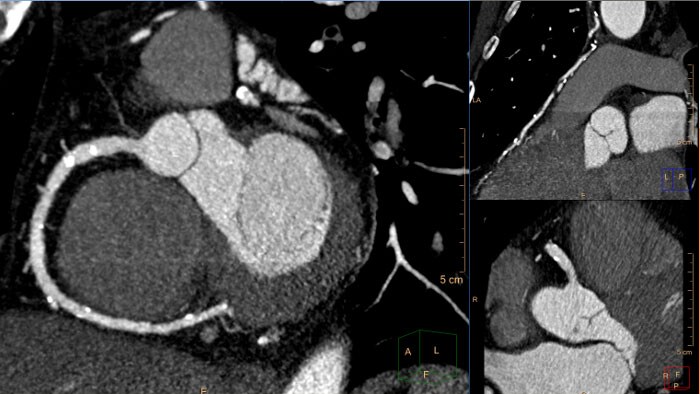

Visualizador de TC cardíaca

A remoção da caixa torácica para exames de TC cardíaca permite a apresentação de uma imagem de volume anatómico 3D do coração e dos grandes vasos sanguíneos aos quais está ligado.